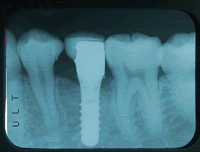

< 術後約一ヶ月半で治療終了 >

インプラントといっても車と同じで様々なものがあります。当院では、スイス製のITIインプラントを用いています。特色は一回法といって手術が一回ですむこと、手術後約一ヶ月半で治療が終わること(GBRなど特殊な治療をしない場合)です。

私は自分でおこなう範囲を決めており無理な手術は極力さけるようにしております。範囲を超えた場合は大学病院やさらに専門性に長けた先生を紹介させていただきます。車で例えればインプラントは高性能のスポーツカーです。ドライブテクニックがある人が、運転すれば素晴らしい性能を引き出せますが、未熟な人が運転すると返って大事故を引き起こしてしまいます。インプラント治療は物を買うわけではありませんので、費用だけで決められるのは不安があるかもしれません。